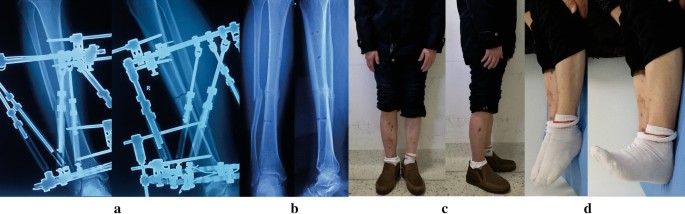

All patients (100%) achieved bone union with a mean time of 26 weeks (range 15 to 52 weeks). Primary fracture union was observed in 28 patients (82%) with a mean time of 24 weeks (range 15 to 32 weeks). Three patients (9%) suffered bone loss due to debridement and were successfully managed by acute shortening and relengthening, the mean time to healing was 31 weeks (range 28 to 35 weeks). In these 3 cases, bone lengthening and anatomic alignment were achieved by the HEF strut adjustments. The other 3 patients (9%) required further intervention procedures and united at a mean of 43 weeks (range 37 to 52 weeks). All patients were followed for an average of 15 weeks (range 12 to 26 weeks) after removing the TSF. (Figs. 1, 2, 3, 4).

Images of the same patient shown in Fig. 1. a Radiographs after final correction. b Radiographs one months later after removal of TSF. c, d Clinical follow-up images, obtained at 12 months after TSF removal